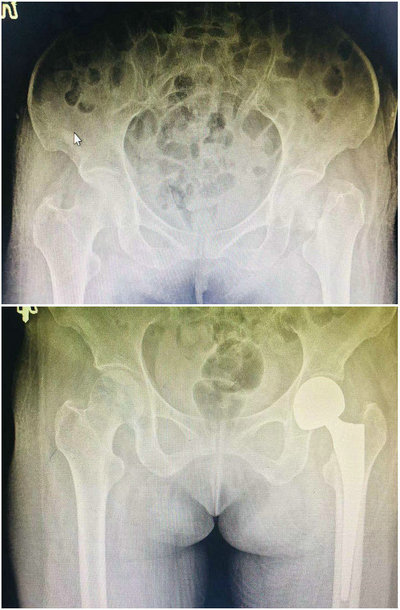

57岁的李女士,因患有家族遗传重症肌无力,平时日常生活受到严重影响,4月14日李女士又不慎摔伤致使左髋关节疼痛,活动受限,在其他医院就诊后诊断为左侧股骨颈骨折(头下型),因患者有肌无力病史,手术风险大,难度高,建议李女士进行保守治疗。但是头下型股骨颈骨折后极可能出现股骨头坏死及骨折不愈合,并且保守治疗需要长期卧床,会出现下肢静脉血栓形成、坠积性肺炎、压疮等并发症的发生危及生命,李女士在家属的陪同下慕名来到骨外科二病区找到李晓光主任。

为提高病人生活质量,李主任建议病人行人工髋关节置换手术治疗,但是病人有肌无力病史,关节置换术后人工关节脱位的风险较大,综合评估病人的病情后,李晓光主任带领骨外科二病区团队选择行左侧股骨经骨折人工股骨头置换手术治疗,对术中可能出现的问题及术后可能出现的并发症等问题,进行了周密的术前讨论,制定了缜密的手术方案。经过骨外科二病区医护团队的努力下,术后第3天,李女士下床借助助行器已经可以自行行走。避免了保守治疗会出现的股骨头坏死,骨折不愈合,以及长期卧床的并发症,同时还可以降低术后关节脱位的风险,效果良好。

术前(上)术后X线检查对比